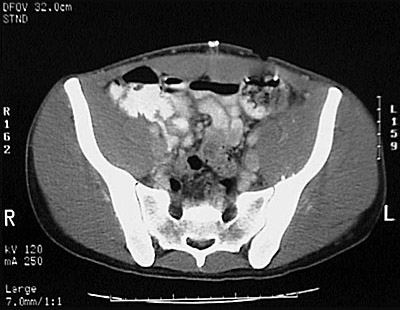

[S2] This is a normal pelvic CT scan with contrast demonstrating the colon and small intestine and right ilium and left ilium and sacrum and right sacroiliac joint and left sacroiliac joint and iliacus muscle and psoas muscle and rectus abdominis muscle and multifidus muscle and gluteus medius muscle and gluteus maximus muscle and gluteus minimus muscle and left internal iliac artery and vein and left external iliac artery and vein in the pelvis.